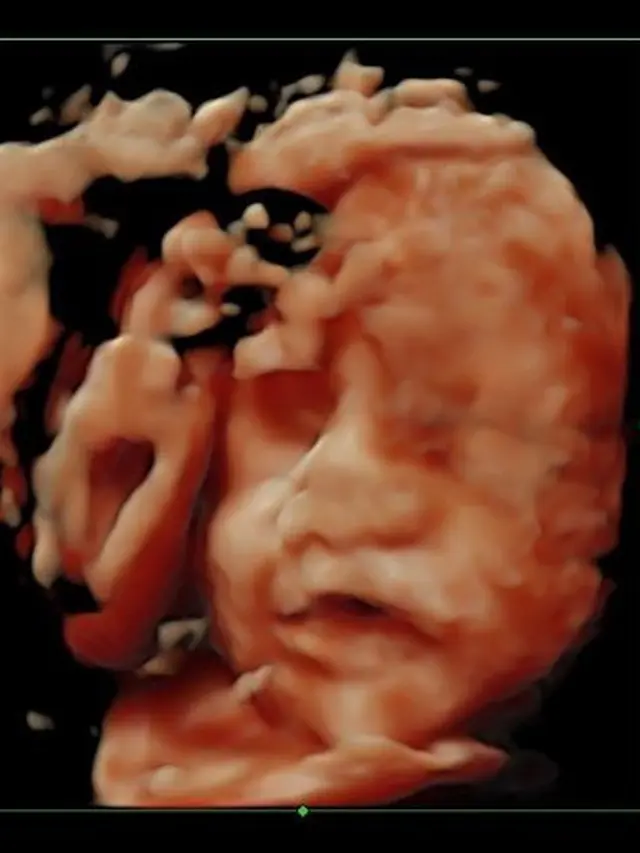

Foto USG

Saat pemeriksaan USG di usia 28 minggu, tampak imej wajah dari janin anak pertamanya tersebut. Faradilla Yoshi pun mengucap antusiasmenya.

"#masyaallahtabarakallah can’t wait to meet you Adek," tuturnya.